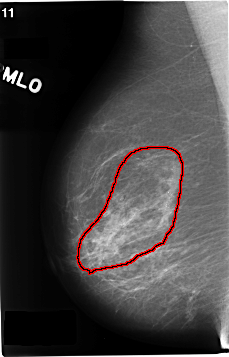

C_0172_1.RIGHT_MLO

RIGHT_MLO LINES 4640 PIXELS_PER_LINE 2976 BITS_PER_PIXEL 12 RESOLUTION 50 OVERLAY

FILE: C_0172_1.RIGHT_MLO.OVERLAY

TOTAL_ABNORMALITIES 1

ABNORMALITY 1

LESION_TYPE CALCIFICATION TYPE PLEOMORPHIC DISTRIBUTION REGIONAL

ASSESSMENT 5

SUBTLETY 5

PATHOLOGY MALIGNANT

TOTAL_OUTLINES 1

BOUNDARY